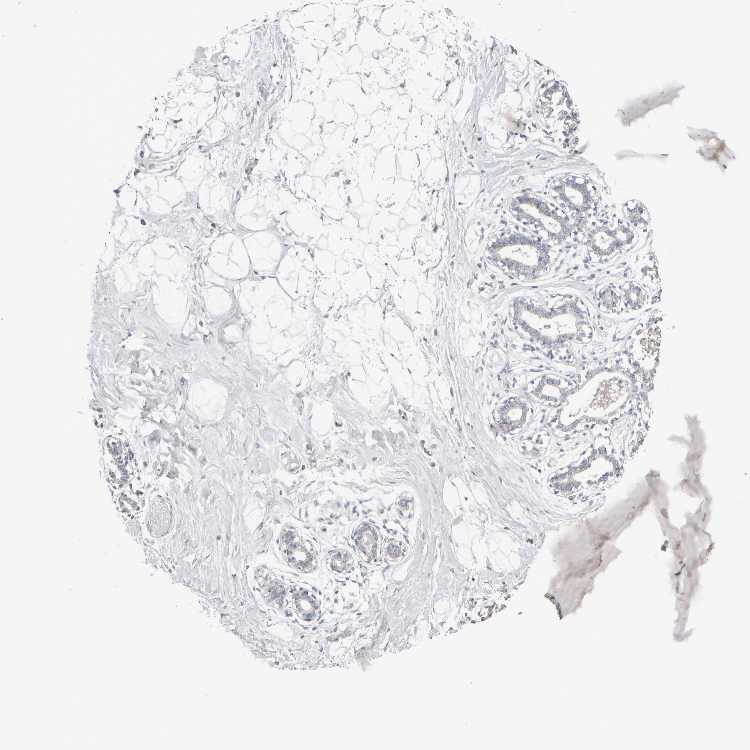

TISSUE PRIMARY DATA BREAST Show tissue menu

BREAST - Antibody stainingi

Antibody staining in the annotated cell types in the current human tissue is reported as not detected, low, medium, or high, based on conventional immunohistochemistry profiling in selected tissues. This score is based on the combination of the staining intensity and fraction of stained cells.

Each image is clickable and will lead to virtual microscopy that enables deeper exploration of all samples and also displays staining intensity scores, fraction scores and subcellular localization as well as patient and tissue information for each sample.

Antibody HPA023094Antibody HPA023660

Adipocytes Not detectedNot detected

Glandular cells HighLow

Myoepithelial cells MediumNot detected